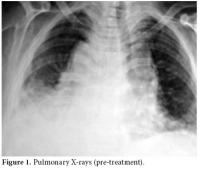

The pericardiocentesis fluid and blood cultures were negative, and the control ECHO was normal in the third and fifth days. The effusion had completely disappeared. Therefore, taking into account all clinical, radiological, and laboratory findings, the patient was diagnosed with DILE due to the use of sulphasalazine. Existing minimal pleural effusion was reported by the pulmonary disease department (figure 7). Liver enzyme and ferritin levels were normal. The other laboratory changes before discharge were as follows: leukocyte count: 18800/mL, Hgb: 12.7 g/dl, CRP: 3.84 mg/L, RF: 37 IU/mL (0-15), ESR: 22 mm/hour, anti-CCP: positive, ANA: negative, anti-histone antibodies: positive, and anti-dsDNA: negative. Urine analysis findings were within normal limits, and the DAS was calculated as 3.06.